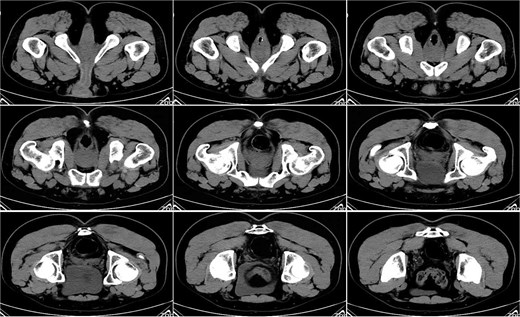

On postoperative Day 21, a follow-up pelvic CT scan indicated local gas accumulation around the rectum, suggesting an absorption phase of the infection (Fig. 4). By postoperative Day 28, a pelvic CT scan demonstrated minor gas accumulation at the anterior edge of the rectosigmoid junction, consistent with infection resolution and gas absorption in the surrounding area (Fig. 5). By postoperative Day 49, a pelvic CT scan revealed no abnormal density shadows in the perianal skin and soft tissues, with preserved fat planes (Fig. 6), indicating complete resolution of the perirectal infection and restoration of normal clinical status.